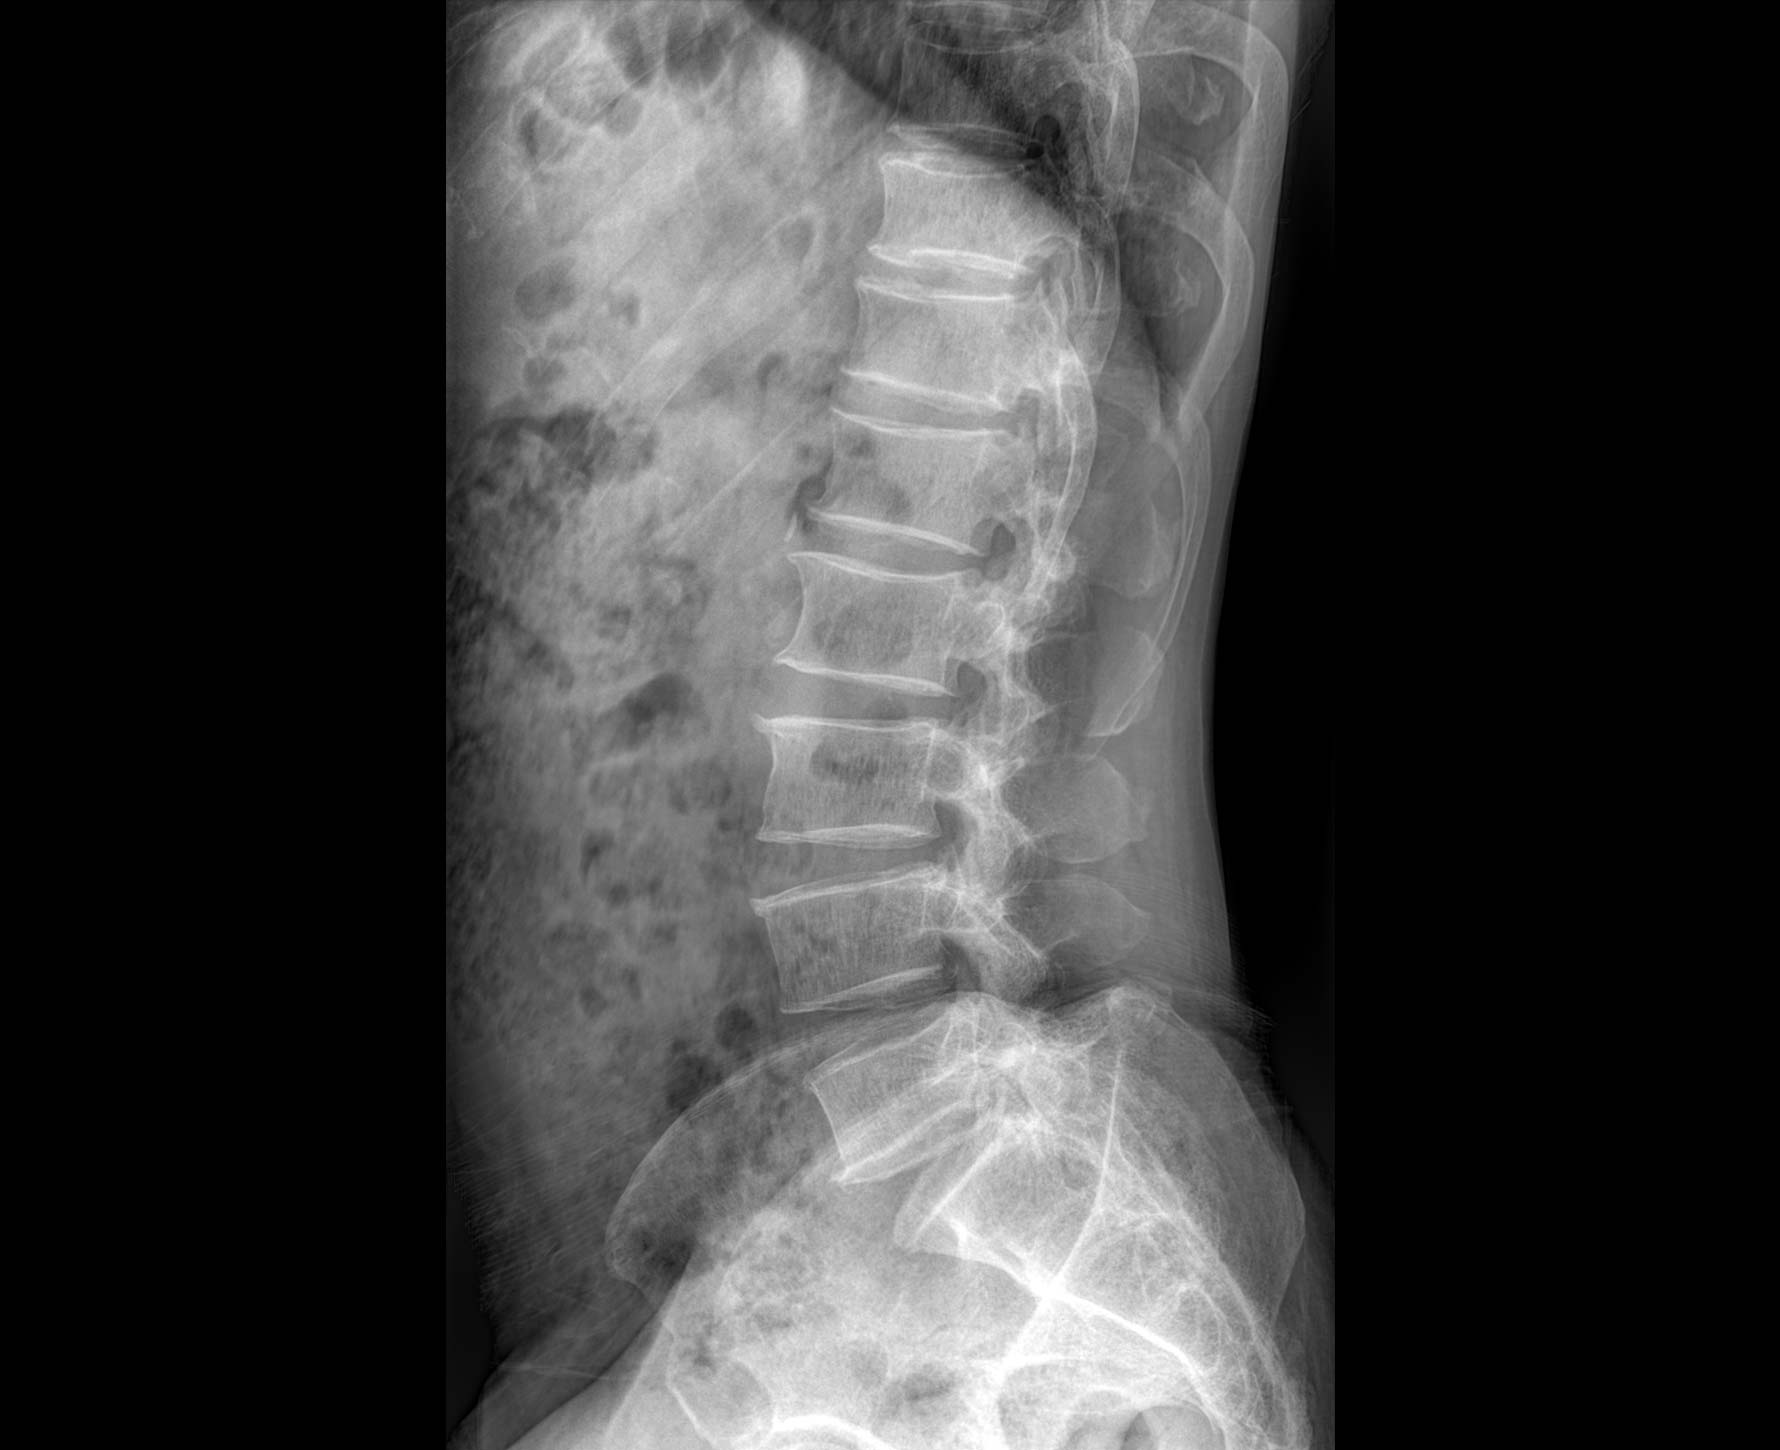

• 拍片

适用于全身各部位摄影

(常规摄影和特殊摄影)